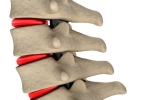

• 颈椎骨质增生酸胀需要治疗吗

颈椎骨质增生酸胀需要治疗吗

颈椎骨质增生酸胀多数情况下无需特殊治疗。症状较轻时可通过物理治疗、药物缓解、姿势调整、颈部锻炼、中医理疗等方式改善。1、物理治疗:热敷或冷敷可缓解局部酸胀感。热敷促进血液循环,每次15-20分钟;冷敷适用于 ...